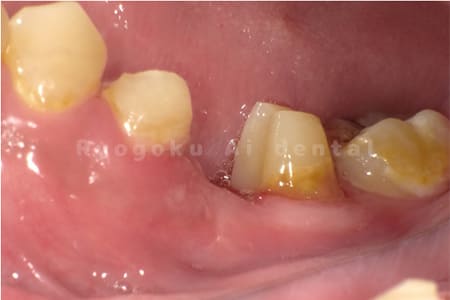

Case02

- 原因

- 重度縁下カリエス、慢性根尖性歯周炎

- 治療期間

- 約3ヶ月(最終補綴装着まで含む)

- 治療内容

- クラウンレングスニング+歯周外科+マイクロエンド

- 治療費用

- 165,000円(最終補綴を除く)

他院で抜歯を宣告された患者様です。歯の根の治療(マイクロエンド)と歯周外科・クラウンレングスニングを行いました。

<リスク・副作用>

手術後は痛み、腫れ、痺れ、青あざなどの副作用が生じます。痛みは痛み止めを処方しますが、腫れ、青あざは1週間程度生じる場合があります。また、部位によっては神経の走行が複雑で、痺れが残り、長期的にお薬を処方する場合があります。